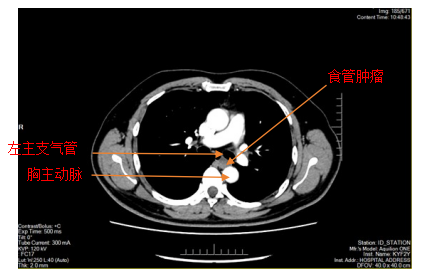

胸部增强CT

患者李某因胸骨后异物感20余天入院,在外院进行胃镜检查提示食管距门齿约26cm处见黏膜下肿瘤,在昆医大附二院超声胃镜提示该肿瘤呈低回声,局限于黏膜下层,固有肌层完整;胸部CT提示该肿瘤直径>2cm,位于食管中下段,增强扫描轻度强化,前与左主支气管相邻,后紧贴胸主动脉,手术过程中稍有不慎就可能发生大出血,危及患者生命,手术难度和风险可想而知。